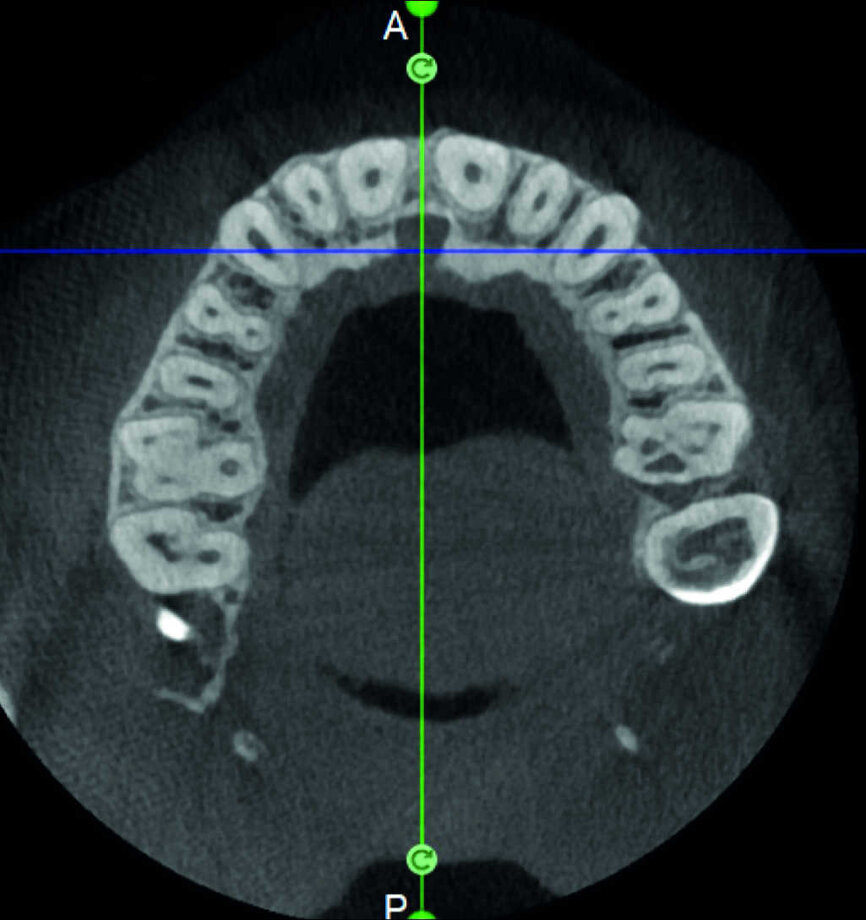

L’évaluation CBCT préopératoire est utile dans les cas nécessitant une approche chirurgicale, non seulement pour confirmer la présence d’une lésion, mais aussi pour planifier l’intervention et, en particulier, identifier le type d’incision chirurgicale à pratiquer, en fonction de la taille et de l’emplacement de la lésion en question (Figs. 23–25). Le cas spécifique présenté dans cet article est caractéristique de cette situation. La radiographie intraorale n’a pas permis de déterminer l’étendue de la lésion, qui touche non seulement la région apicale de la prémolaire, mais aussi un segment édenté en distal. Cette région doit faire l’objet d’un traitement régénérateur, afin de garantir la cicatrisation appropriée de la zone, suivi par la mise en place d’une membrane. Une approche totalement différente de celle requise pour la chirurgie endodontique doit être utilisée pour protéger le lambeau. Les différentes étapes de l’intervention sont illustrées dans les images peropératoires (Figs. 26–28). L’examen CBCT réalisé 12 mois plus tard, confirme la cicatrisation complète de la lésion apicale et la parfaite intégration de la greffe (Figs. 29–31).